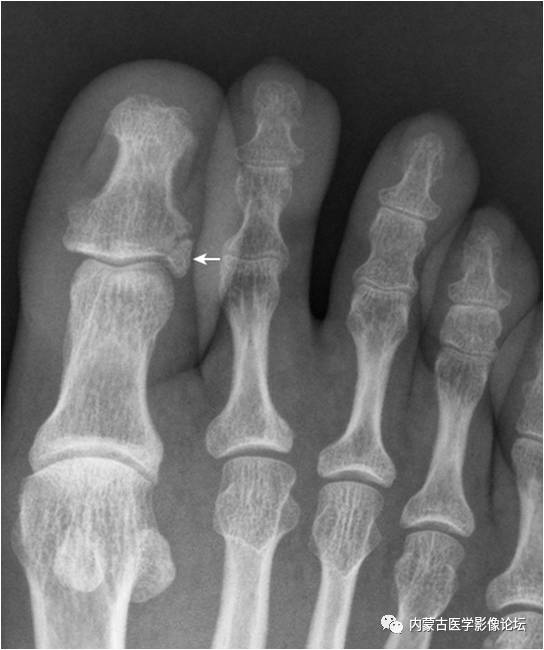

19.拇趾多分籽骨:拇趾内外侧籽骨可表现为二分籽骨(箭)或三分籽骨(箭头),为正常变异,需与籽骨骨折、坏死鉴别。骨折边缘多不规则,坏死密度多不均。

21.足趾副骨:趾跖关节内侧见点状骨性灶(箭),又称关节旁骨,一般无病理意义,但有时可引起邻近骨生长障碍和坏死。要与撕脱骨折鉴别。

22.趾骨骨骺:拇趾远节趾骨骨骺内侧较外侧宽(箭),其与趾骨干骺端间距离较宽(箭头),为正常表现,勿误认为是骺离骨折。近节趾骨骨骺可呈扁平状,并密度增高,亦为正常表现,勿误认为坏死。

32.拇趾撕脱骨折:该例为陈旧性撕脱骨折。拇趾外侧基底部部分撕脱,虽游离骨片(箭)边缘清晰,但与基底部有很好的对合,可与关节旁骨相鉴别。

33.籽骨骨折:拇趾外侧籽骨形态不完整,内侧见透亮线(箭),两部分骨对应缘不规整,无硬化缘,与二分籽骨的边缘骨质致密不同。内侧籽骨完整(箭头)。